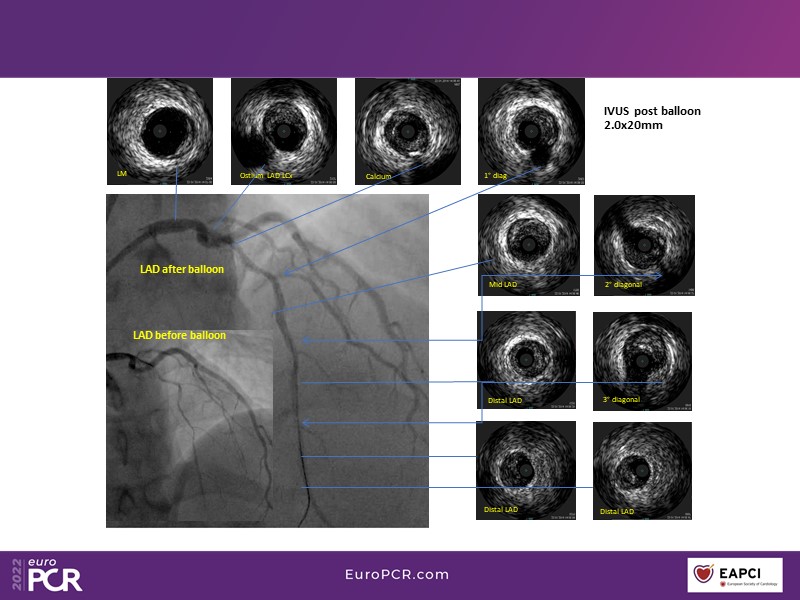

DCB and the possibility of a clean vessel

This EuroPCR 2022 session aims to show, based on real-life cases, that even complex coronary disease can be treated without the need for permanent coronary stents. Learn how to prepare the vessel, deliver the therapy, and assess immediate outcomes after "DCB-alone" PCI, discuss de novo, small vessels, and in-stent restenosis cases with follow-up, define what may be an optimal long-term result, refresh the scientific bases, and understand the clinical benefits and safety of paclitaxel DCBs.

- To know how to prepare the vessel, deliver the therapy and evaluate the immediate results after "DCB-alone" PCI

- To discuss de novo, small vessels and in-stent restenosis cases with follow-up and define what may be an optimal long-term result